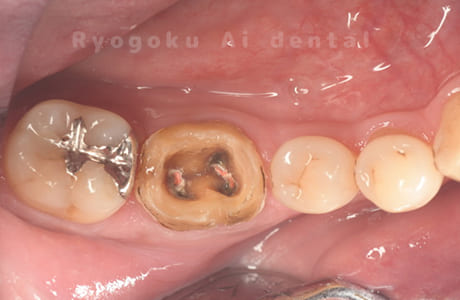

Case02

- 縁下カリエス、慢性根尖性歯周炎、不良補綴

- 治療期間

- クラウンレングスニング、マイクロエンド、フルジルコニアクラウン

- 約840,000円

虫歯が神経まで及ぶと共に、歯茎の中まで虫歯が及んでいました。根の治療(マイクロエンド・根管治療)を行なった後、クラウンレングスニング・歯周外科を行い、ジルコニアの被せ物を行った患者様です。

<リスク・副作用>

過度の咬合や衝撃で割れることがあります。